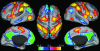

During performance of attention-demanding cognitive tasks, certain regions of the brain routinely increase activity, whereas others routinely decrease activity. In this study, we investigate the extent to which this task-related dichotomy is represented intrinsically in the resting human brain through examination of spontaneous fluctuations in the functional MRI blood oxygen level-dependent signal. We identify two diametrically opposed, widely distributed brain networks on the basis of both spontaneous correlations within each network and anticorrelations between networks. One network consists of regions routinely exhibiting task-related activations and the other of regions routinely exhibiting task-related deactivations. This intrinsic organization, featuring the presence of anticorrelated networks in the absence of overt task performance, provides a critical context in which to understand brain function. We suggest that both task-driven neuronal responses and behavior are reflections of this dynamic, ongoing, functional organization of the brain.